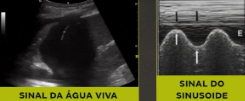

O que significa o sinal da água viva no USG?

Significa derrame plaural (vemos pulmão flutuando em meio líquido)

= corresponde ao sinal do sinusoide (modo M)